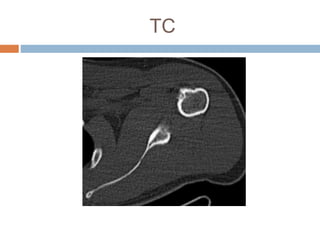

Este documento presenta el caso de un hombre de 37 años con dolor en el hombro izquierdo durante 7 meses. Las imágenes mostraron un nido tumoral en el hombro con características de osteoma osteoide. El osteoma osteoide es un tumor benigno que ocurre comúnmente en varones menores de 30 años y se caracteriza por un nido óseo y esclerosis reactiva. Fue tratado mediante excisión quirúrgica.